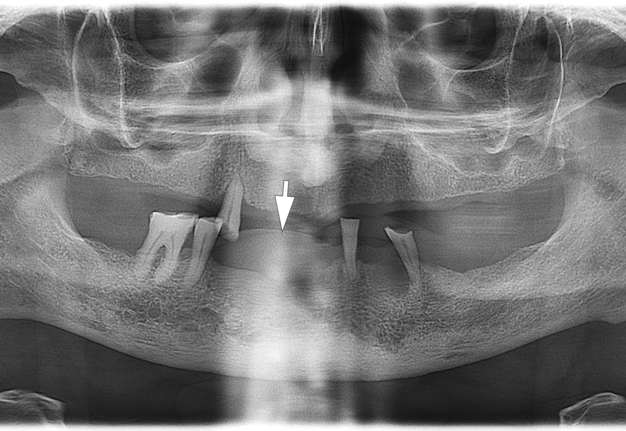

A radiographic examination was performed to assess the condition of the bone tissue and teeth, and an USG was performed to assess the structure and vascularization of the soft tissue lesion. The panoramic radiograph (Fig 2) showed a dome-shaped radiopacity rising above the alveolar ridge of the edentulous area of the anterior mandible.

The simplest method of diagnosing the oral cavity is panoramic radiography. It is also appropriate in the case of PGCG, but it solves a limited range of issues, namely, assessing the condition of neighboring teeth and the presence of bone resorption.

In our case, it was difficult to reliably determine the areas of ossification in the projection of radiopacity (i.e., PGCG) on the orthopantomography. This can most likely be explained by an insufficient level of ossification. In other cases, newly formed bone tissue in the projection of the PGCG was visible radiologically [23].